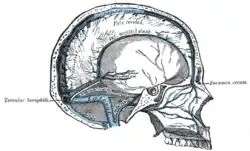

Os seios venosos durais (também chamados de seios durais, seios cerebrais ou seios cranianos) são canais venosos encontrados entre as camadas de dura-máter no cérebro.[1]

Eles recebem sangue das veias internas e externas do cérebro,

Recebem ainda líquido cefalorraquidiano (líquor) do espaço subaracnóideo através de granulações aracnoideias que se encontram presentes nas cavidades areolares da dura máter (também chamadas de saculações) (apenas no seio sagital superior).

Drenam na veia jugular interna.

Seios venosos

| Nome | Drena para |

| Seio sagital inferior | Seio reto |

| Seio sagital superior | Confluência dos seios |

| Seio reto | Confluência dos seios |

| Seio occipital | Confluência dos seios |

| Confluência dos seios | Seio transverso |

| Seio cavernoso | Seios petrosos superior e inferior |

| Seio transverso | Seio sigmóide |

| Seio petroso superior | Seio sigmóide |

| Seio petroso inferior | Veia jugular interna |

| Seio sigmóide | Veia jugular interna |